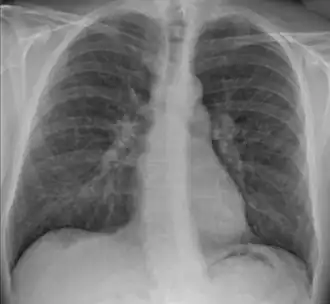

Radiographie du thorax montrant un infiltrat interstitiel.

• stade 2 : adénopathies médiastinales et infiltrat/micronodules interstitiels,

• stade 3 : infiltrat/micronodules interstitiels sans adénopathies médiastinales,